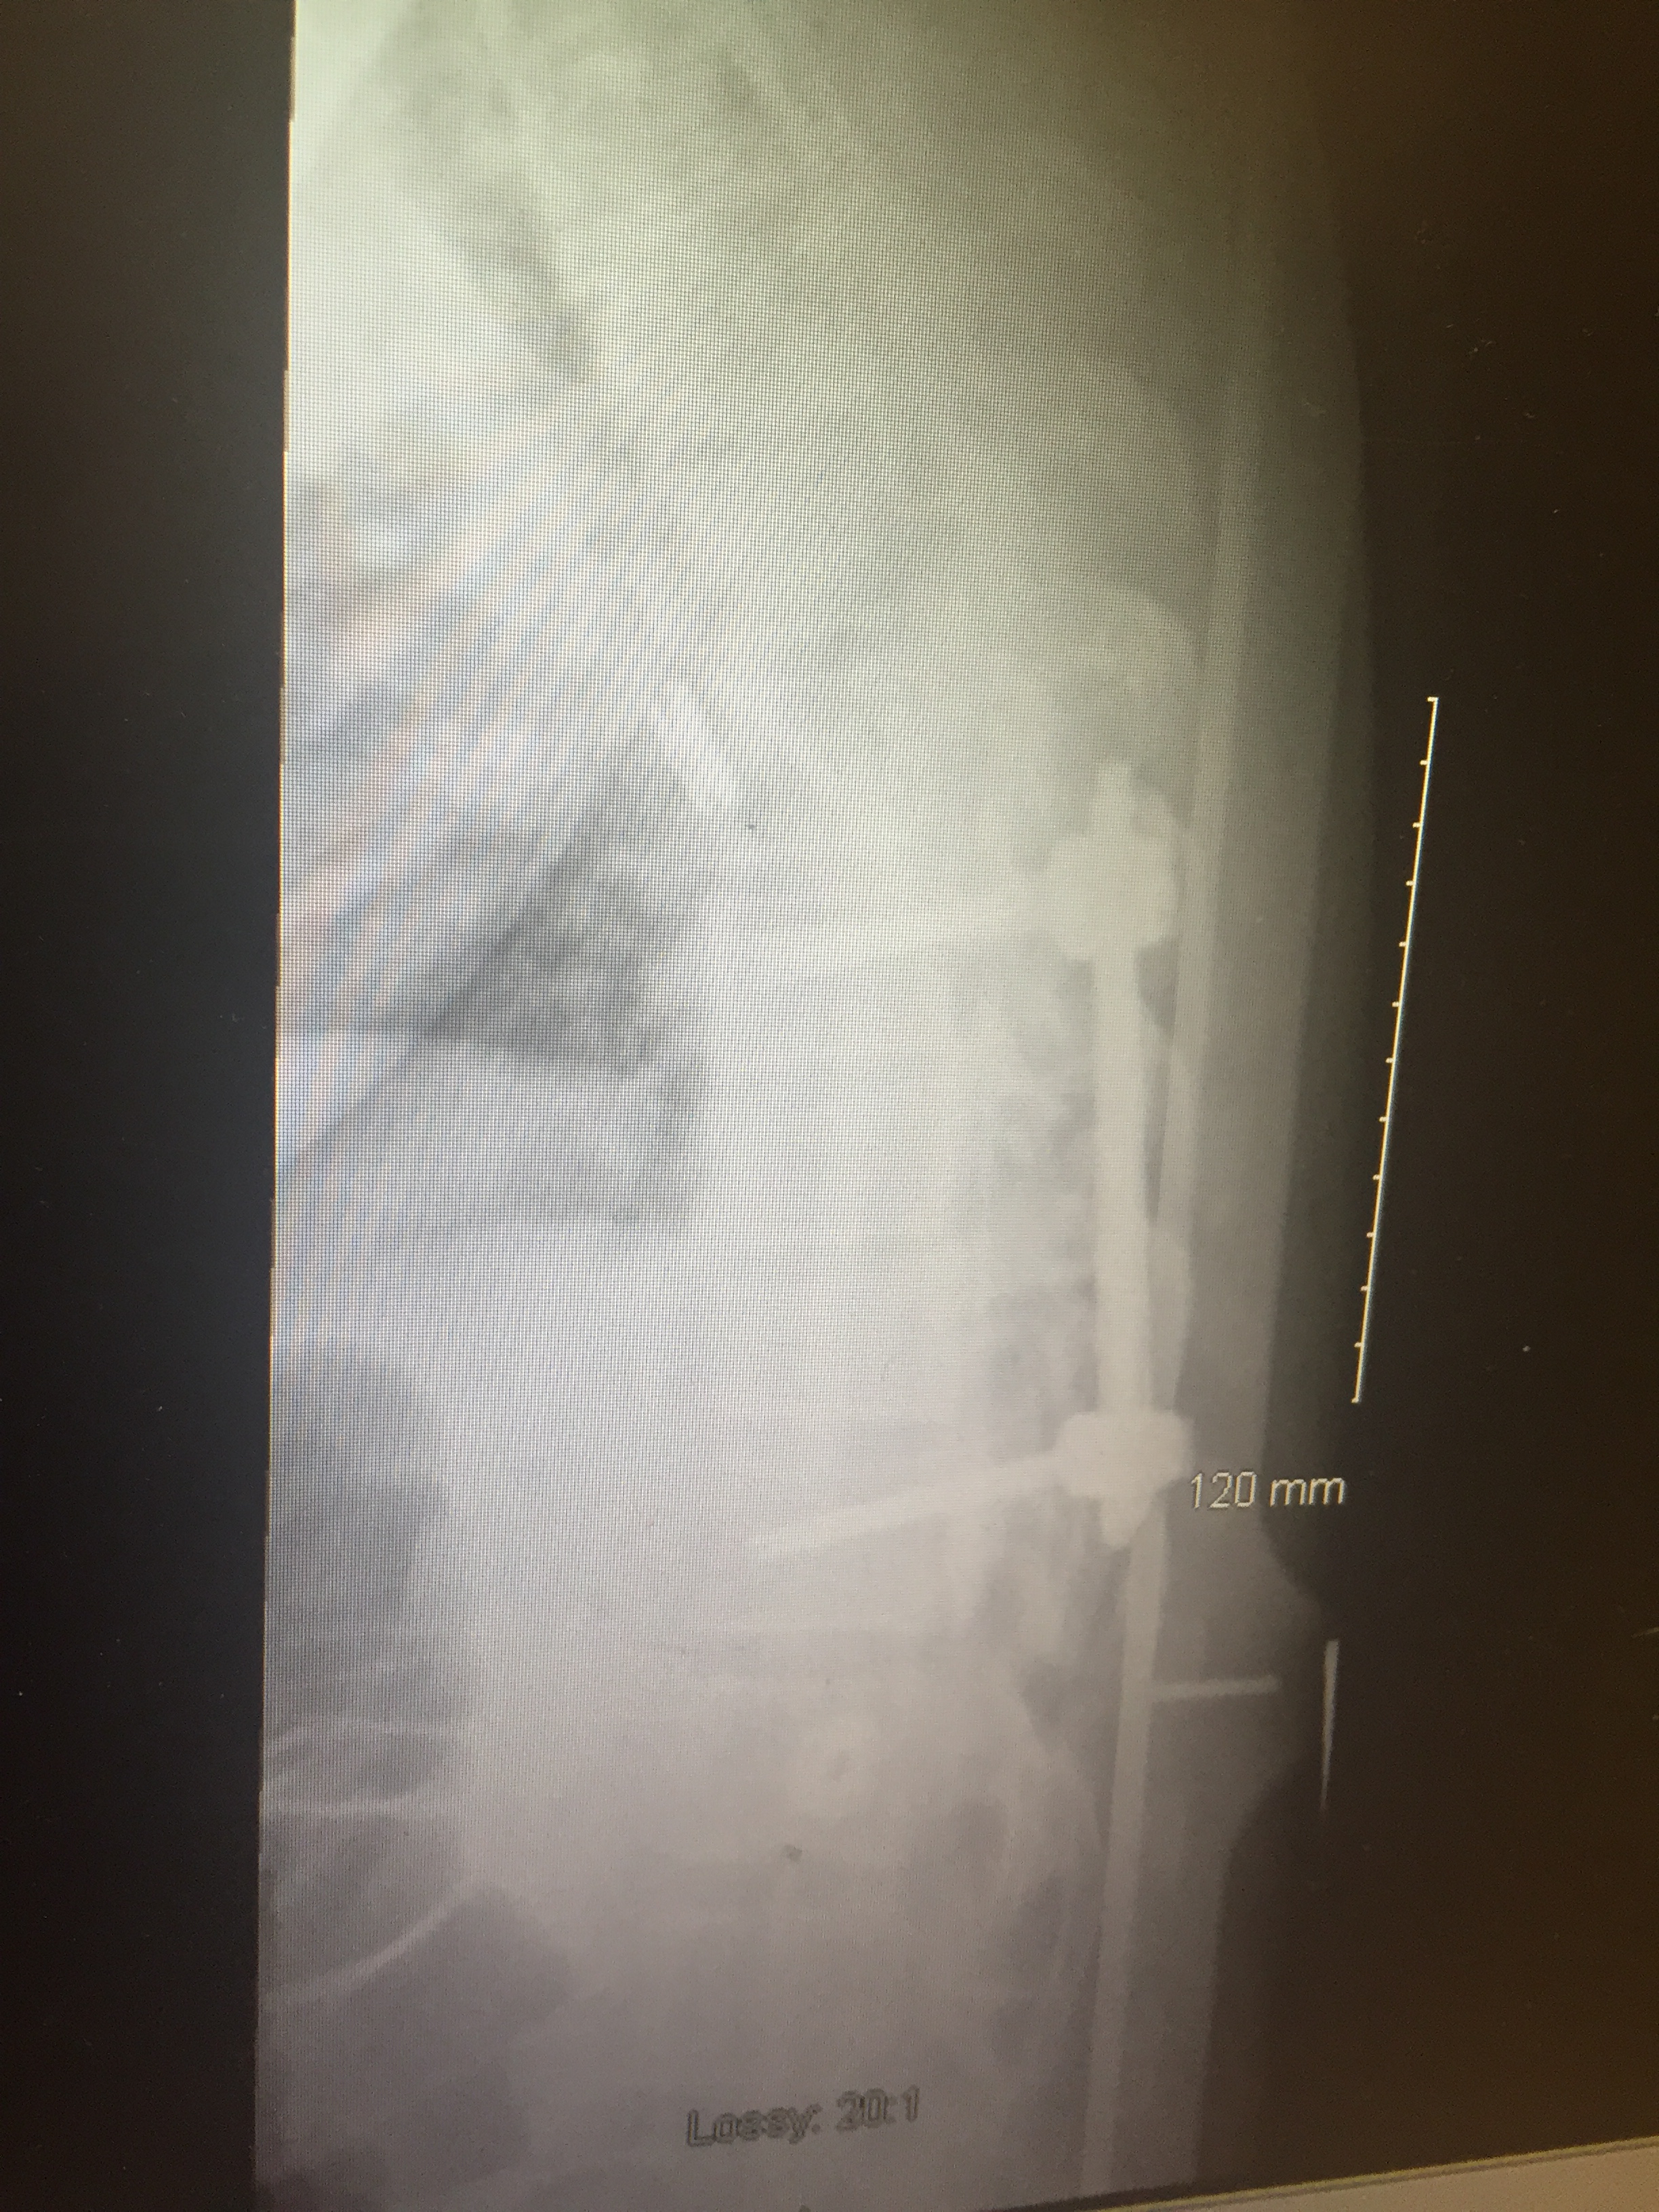

Adam: I broke my T8 to T11. That’s fine so they put pins in there, I broke my iliac crest, so the top of my hipbone sheared right off and then as they said that I had open lacerations which are actually the biggest concern to them because of infection. There’s rock fall in there, but it was down to the bone across all my hip. Which is pretty horrible and the other parts of me were sore but they weren’t as critical.

The one thing that I found after the fact, there is actually two anaesthesiologists who were working at the hospital and one of them thought that all they would work on is my hip to start and then they would come back and do my spine at a later date because it wasn’t critical. The second anaesthesiologist was like no, this person is young and healthy so we’re just going to do both now, he can handle eight hours of surgery.